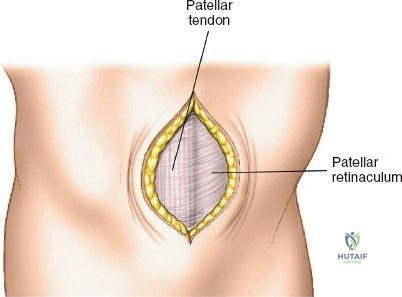

- Incision: A short, vertical incision (typically 2-3 cm) is made over the proximal tibia. This is commonly a midline incision, but some surgeons prefer a parapatellar approach.

The incision should be adequate to allow clear access to the entry point and accommodate the targeting jig. The patellar tendon can be carefully split longitudinally or approached paramedially (medial or lateral to the tendon). - Entry Point Determination: The ideal entry point is crucial for proper nail alignment and preventing iatrogenic damage. It is typically located on the anterior cortex of the tibia, just medial to the lateral edge of the patellar tendon, distal to the articular surface of the tibial plateau.

- Fluoroscopic Guidance: Use an Awl or K-wire under AP and lateral fluoroscopy to confirm the entry point. The AP view should show the wire positioned to align with the central axis of the medullary canal. The lateral view should show the wire in line with the anterior cortex, avoiding a posterior entry which can damage the posterior cortex and lead to malalignment.

- Patellar Tendon Protection: Ensure the entry reamer or awl does not scrape the posterior aspect of the patella or damage the articular cartilage.